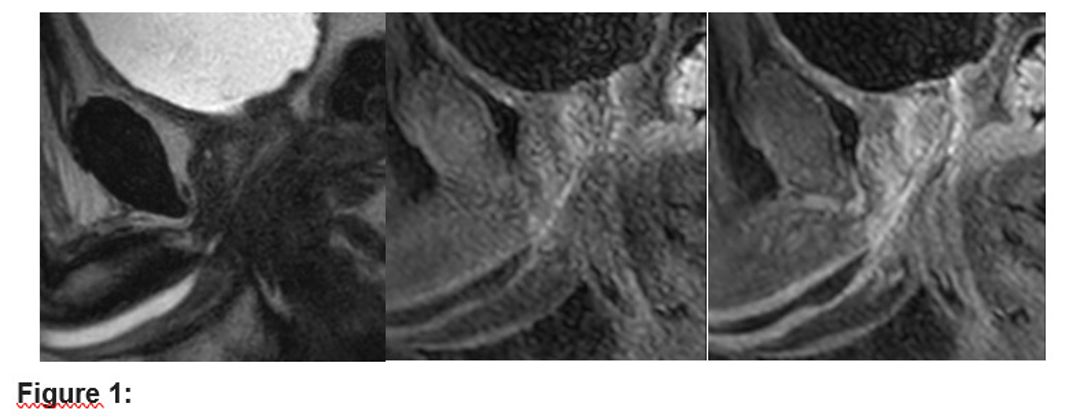

Figure 2

1.	Case 1: A 62-year-old male with recurrent urethral strictures after-coronary bypass surgery and internal urethrotomy. MRI revealed complete occlusion of the distal prostatic urethra and partial stenosis in the proximal bulbous urethra. Anastomotic urethroplasty was successfully performed, excising a 2 cm fibrotic segment.

2.	Case 2: A 63-year-old male post-liver transplant with a recurrent obliterative urethral stricture. MRI and retrograde urethrography confirmed a 2.5 cm stricture in the bulbous urethra, leading to an end-to-end anastomotic urethroplasty after excision of the stricture.

3.	Case 3: A 58-year-old male with a complex stricture, thought to be post-traumatic, was diagnosed with a non-traumatic obliterative stricture. MRI identified a 7 mm stenotic segment in the distal penile urethra. Urethroplasty was performed, addressing the complex stricture with an appropriate surgical approach.

The results emphasize the role of MRI in providing detailed and reliable anatomical information for complex non-traumatic obliterative urethral strictures. In each case, MRI effectively identified the location, length, and extent of the strictures, which were critical in planning the surgical approach. MRI was particularly useful in detecting fibrosis and soft tissue involvement that might not have been fully visible with traditional methods like retrograde urethrography. Moreover, MRI was essential in guiding surgeons to perform appropriate urethroplasty techniques, such as end-to-end anastomotic repairs, thus improving surgical outcomes.

MRI also demonstrated its superior soft tissue resolution compared to other imaging methods, highlighting its potential for better evaluating spongiofibrosis and periurethral tissues, which are cruical in urethral stricture management. The ability to assess the urethra without radiation exposure was another significant advantage, especially in patients requiring multiple imaging studies.